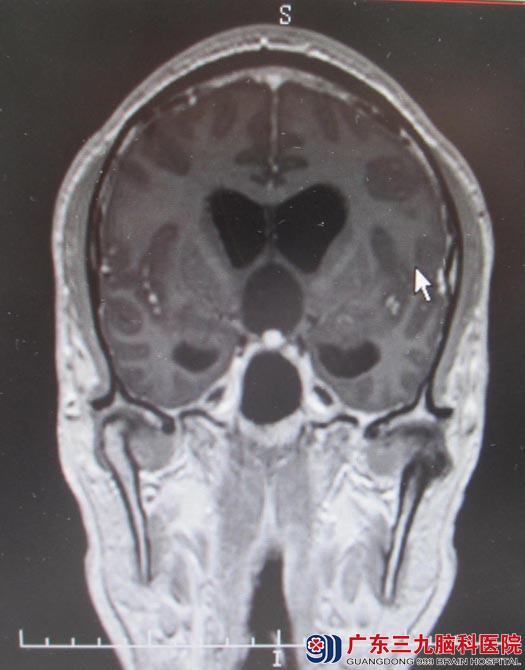

28岁的小舟一个月前开始出现头痛,头晕等症状。最近发作的频率逐渐增高,起初以为是工作压力大,疲劳导致,一直吃药调理,但不见好转。有一天在上班时突然出现剧烈头痛、呕吐、神志不清。被同事紧急送往医院,头颅MRI提示鞍区囊实性占位,颅咽管瘤可能性大,肿瘤大小为34.5mm×36.5mm×24.5mm,梗阻性脑积水。

▲手术前